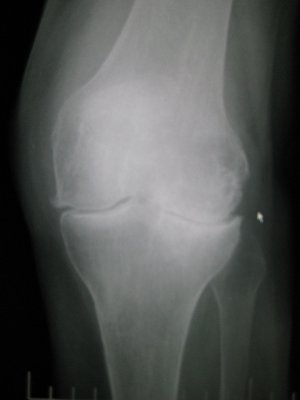

The first test you can expect is an x-ray of your knee which is taken from various angles to provide an accurate visualization of the damage in your joint. If the physician suspects damage to ligaments or a meniscus, you may also undergo an MRI (Magnetic Resonance Imaging).